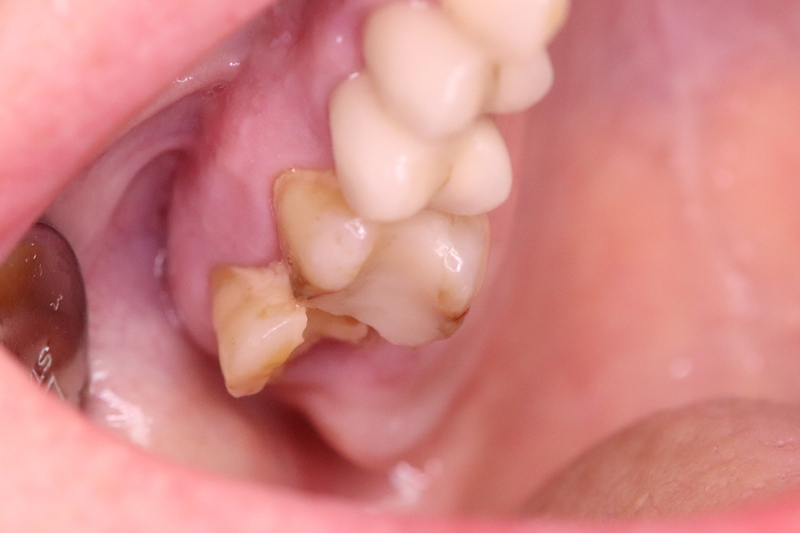

OK 17

Entfernung Zahn 17, Augmentation DentOss grob, 6 und 9 Tage danach, Situation + RÖ.